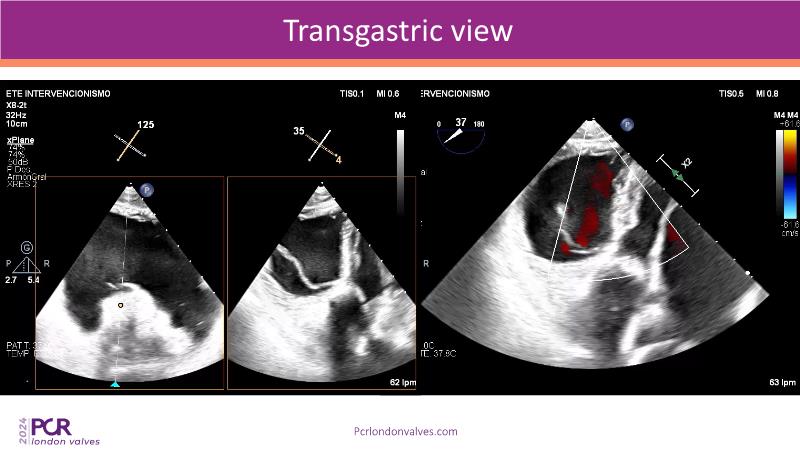

This session examines two compelling cases: a 78-year-old woman with paroxysmal atrial fibrillation, chest trauma, an osteoporotic sternum fracture, and NYHA II exertional dyspnoea, and an 82-year-old man with chronic three-vessel coronary artery disease, bradycardic AF, peripheral arterial disease, spinal stenosis, and chronic kidney disease. Through their study, discover the intricate anatomy of atrioventricular valves, the therapeutic challenges they pose, and the growing significance of transcatheter edge-to-edge repair (TEER) therapies. The discussion also highlights the value of multidisciplinary strategies in managing complex valve diseases effectively.